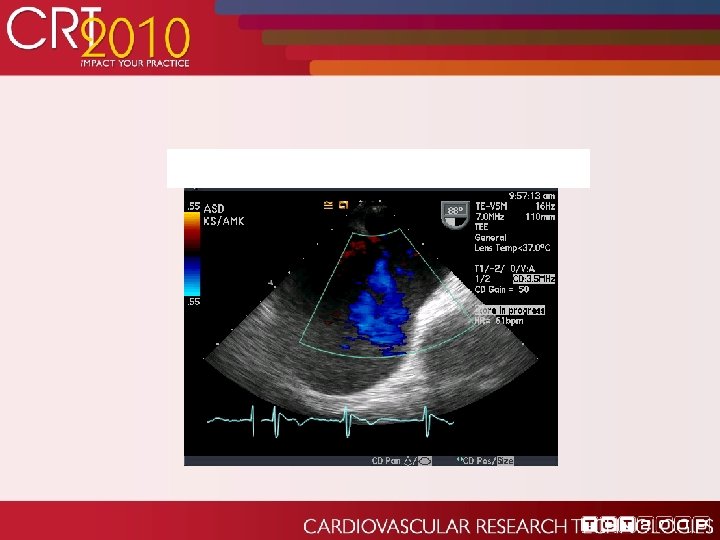

Echo post-procedure: